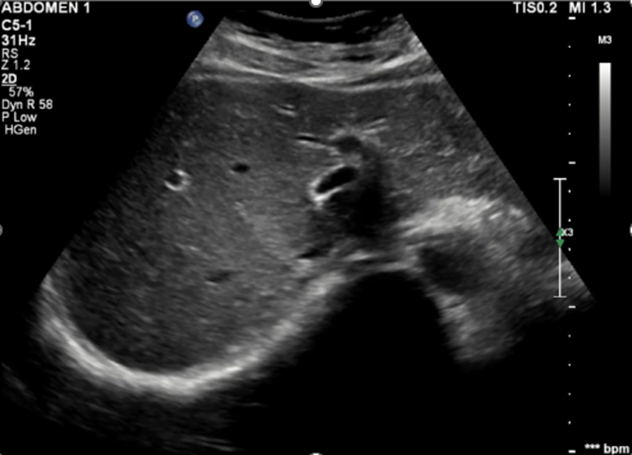

45세 여자가 간기능 이상으로 내원하였습니다. 음주력과 건강식품 복용력은 없었습니다. 혈액검사와 복부 초음파 소견은 아래와 같았습니다. [그림 1]

[그림 1] 복부 초음파 검사

Parenchymal coarseness, mild